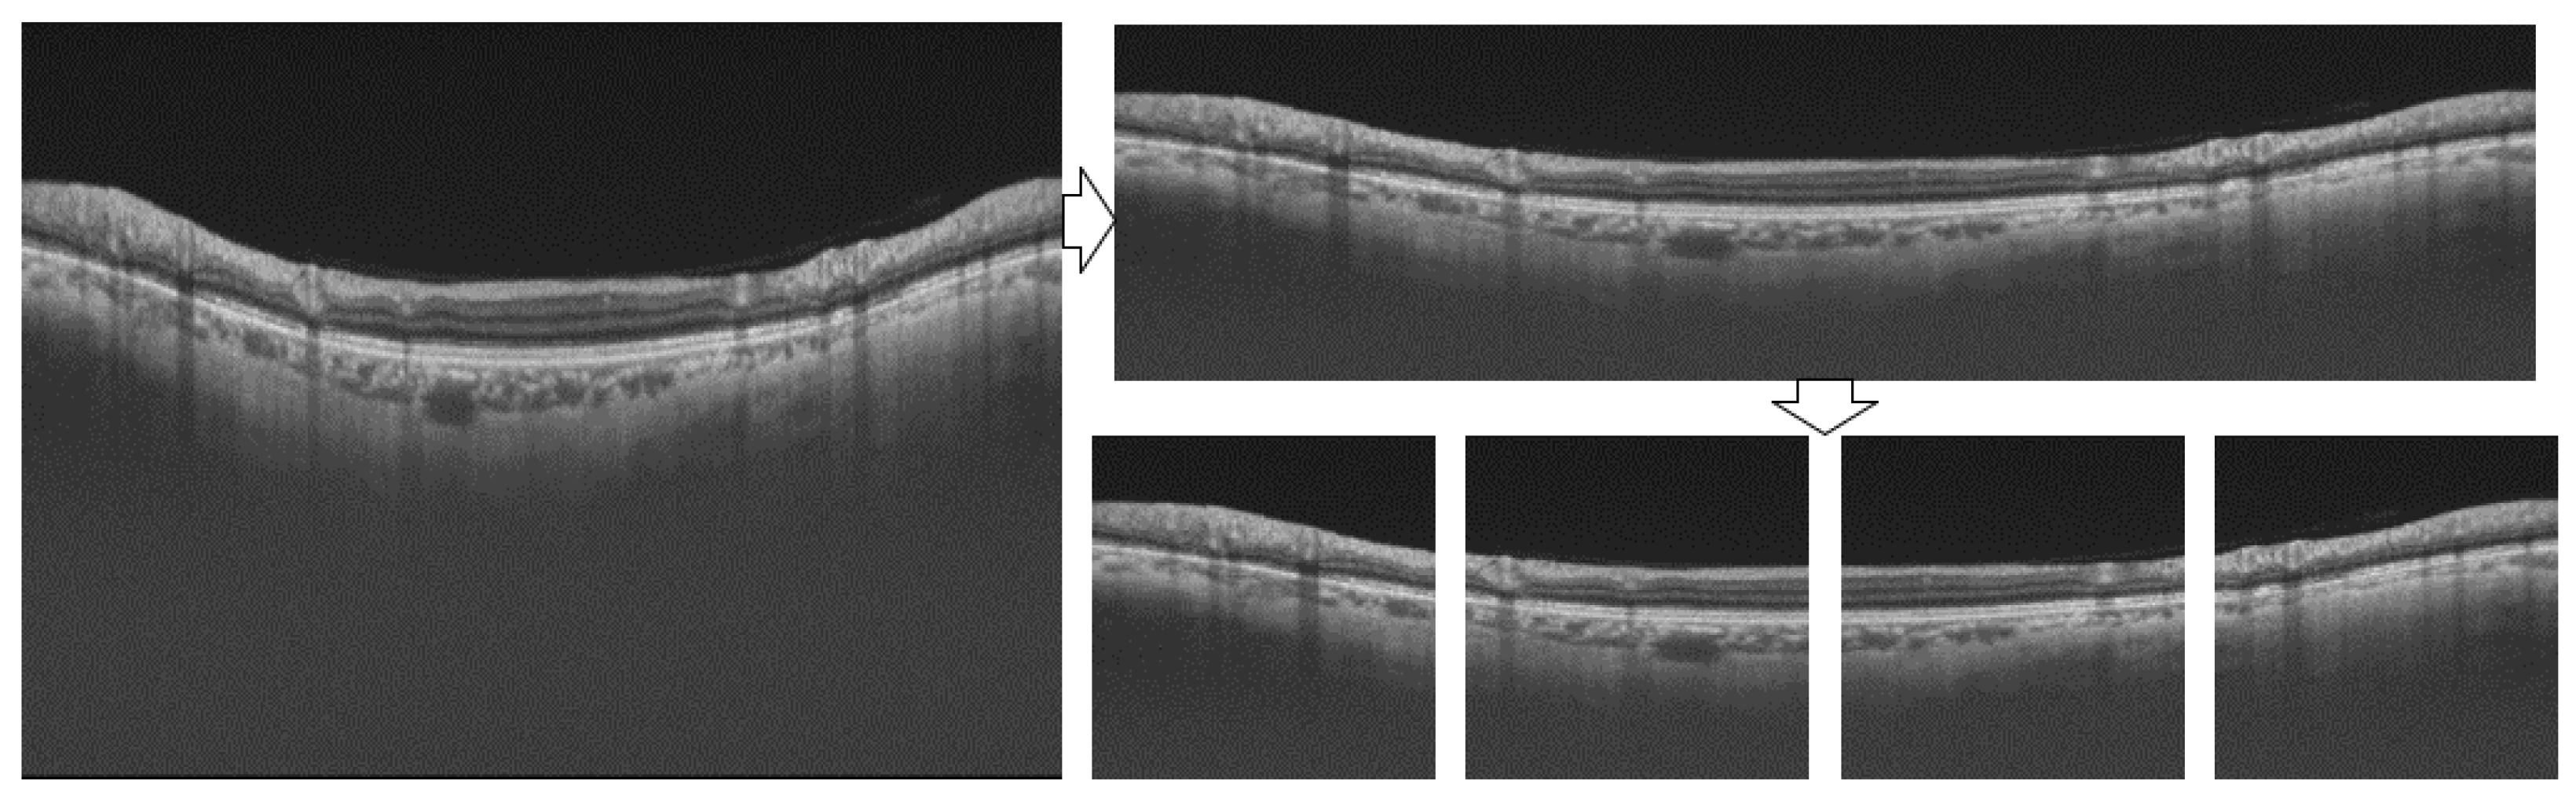

4.1. Dataset

4.2. Image Processing

4.2.1. Pre-Processing

4.2.2. Post-Processing